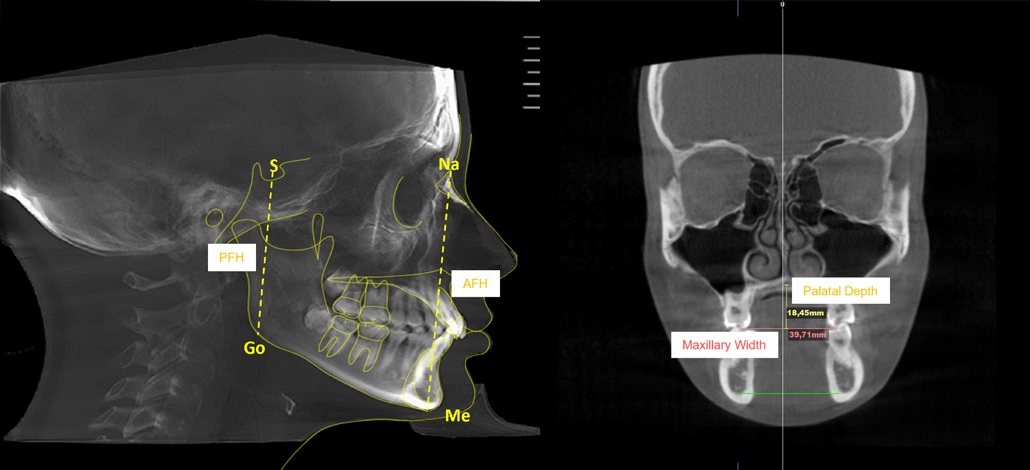

Orthodontic tracing was performed in the mid-sagittal plane slice using the same software. Cephalometric tracing assessed the following variables: anterior facial height (Na-Me), posterior facial height (S-Go), maxillary width, and palatal depth (Figure 1).

The facial biotype was assessed using the VERT index proposed by Ricketts, which entails five cephalometric measurements (facial axis, facial depth, mandibular plane, anteroinferior facial height, and mandibular arch) and classifies the face into six types: severe brachyfacial, brachyfacial, mesofacial, light dolichofacial, dolichofacial, and severe dolichofacial.15